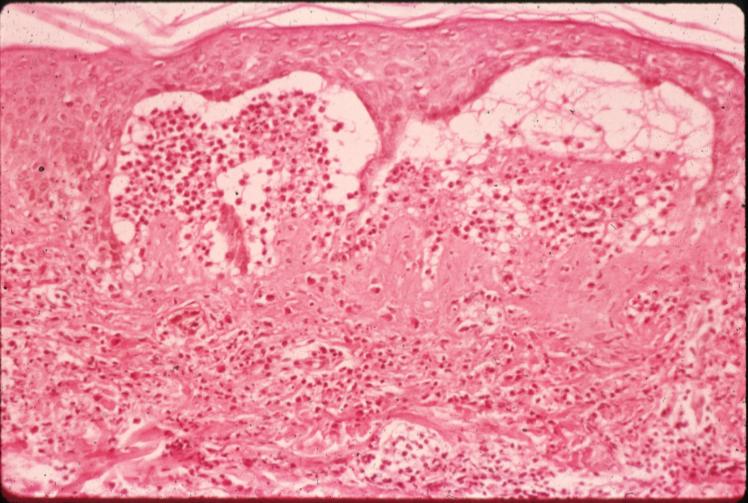

Histopathology.

In early lesions, papillary dermal edema in combination with a cell-poor or cell-rich perivascular lymphocytic and eosinophilic infiltrate is present. The blister arises at the dermal-epidermal junction . In the cell-rich pattern, which correlates clinically with blisters arising on erythematous skin , eosinophilic papillary abscesses may develop with numerous perivascular and interstitial eosinophils intermingled with lymphocytes and neutrophils in the superficial and deep dermis. Early lesions may have the histologic features of eosinophilic cellulitis (Well’s syndrome). Eosinophilic spongiosis may occur. The cell-poor pattem is observed

when blisters develop on relatively normal skin , in which there is usually a scant perivascular lymphocytic infiltrate with few eosinophils, some scattered throughout the dermis and others near the epidermis. The blister contains few inflammatory cells. Epithelial migration and regeneration may result in an intraepidermal split in older blisters. Similar to pemphigus vegetans, a hyperplasia of the epidermis, subepidermal bullae, and accumulations of eosinophils and lymphocytes may be seen.